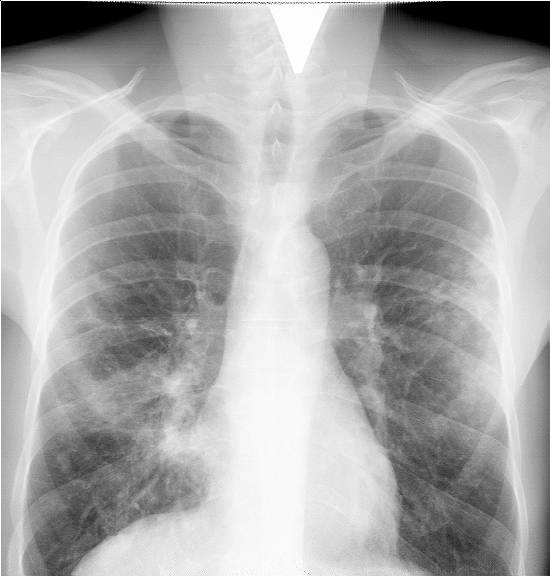

Исследование рентгеном легких: Обычно очаговые или сегментарные затемнения легочной ткани наблюдаются в нижних частях легких с нечеткими и размытыми внешними границами.

- Исследование грудной клетки методом рентгенографии в двух проекциях

Для определения точного диагноза необходимо провести рентгеноскопию легких и два клинических анализа.

Необходимо подчеркнуть, что изменения на рентгенограмме становятся заметными ближе к концу второй или третьей недели, а иногда и позже. Симптомы очаговой пневмонии, вызванной стрептококками, могут привести к образованию абсцесса и эмпиемы плевры.

Для обеспечения точности результатов анализов необходимо выполнить рентгенографию грудной клетки или компьютерную томографию.

При проведении рентгеновского обследования можно обнаружить участки затемнения. Если на рентгеновском снимке затронуты несколько сегментов и видно, как они объединяются в один более крупный, это указывает на наличие очагово-сливной пневмонии. Симптомы этого вида пневмонии более сложны и выражены более ярко, проявляются в форме дыхательной недостаточности и признаков отравления. По клиническим проявлениям очагово-сливная пневмония напоминает крупозное воспаление лёгких и всегда требует госпитализации в стационаре.

Изучение рентгеновскими снимками грудной клетки и проведение компьютерной томографии являются важными исследованиями с множеством информации. Обычно выявляют очаговые темные участки на заднем плане инфильтрации как в области бронхов, так и вокруг сосудов.